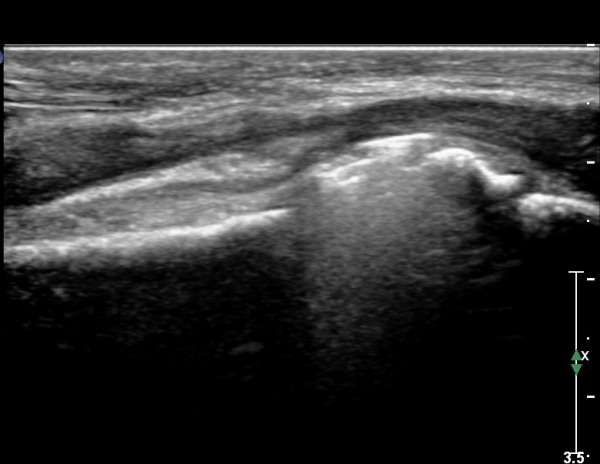

¾Æ·§ÆÈ ÇϺκΠȾ´Ü¸é°Ë»ç¿¡¼­ Àü°ñ°£ ½Å°æ Áö¹è¸¦ ¹Þ´Â  PQ ¿¡¼­ ½Å°æ¸¶ºñ ¼Ò°ß(°í¿¡ÄÚ ±ÙÀ§Ãà)À»

º¸ÀÌÁö ¾ÊÀ¸³ª  FPL ÈûÁÙÀÇ Àú¿¡ÄÚ ºÎÁ¾ÀÌ °üÂûµÇ°í(»çÁø 2, 3) ³»°íÁ¤¹°ÀÌ FPL °ú Á¢ÃËÇϰí ÀÖÀ½ÀÌ °üÂûµÊ(»çÁø 3)